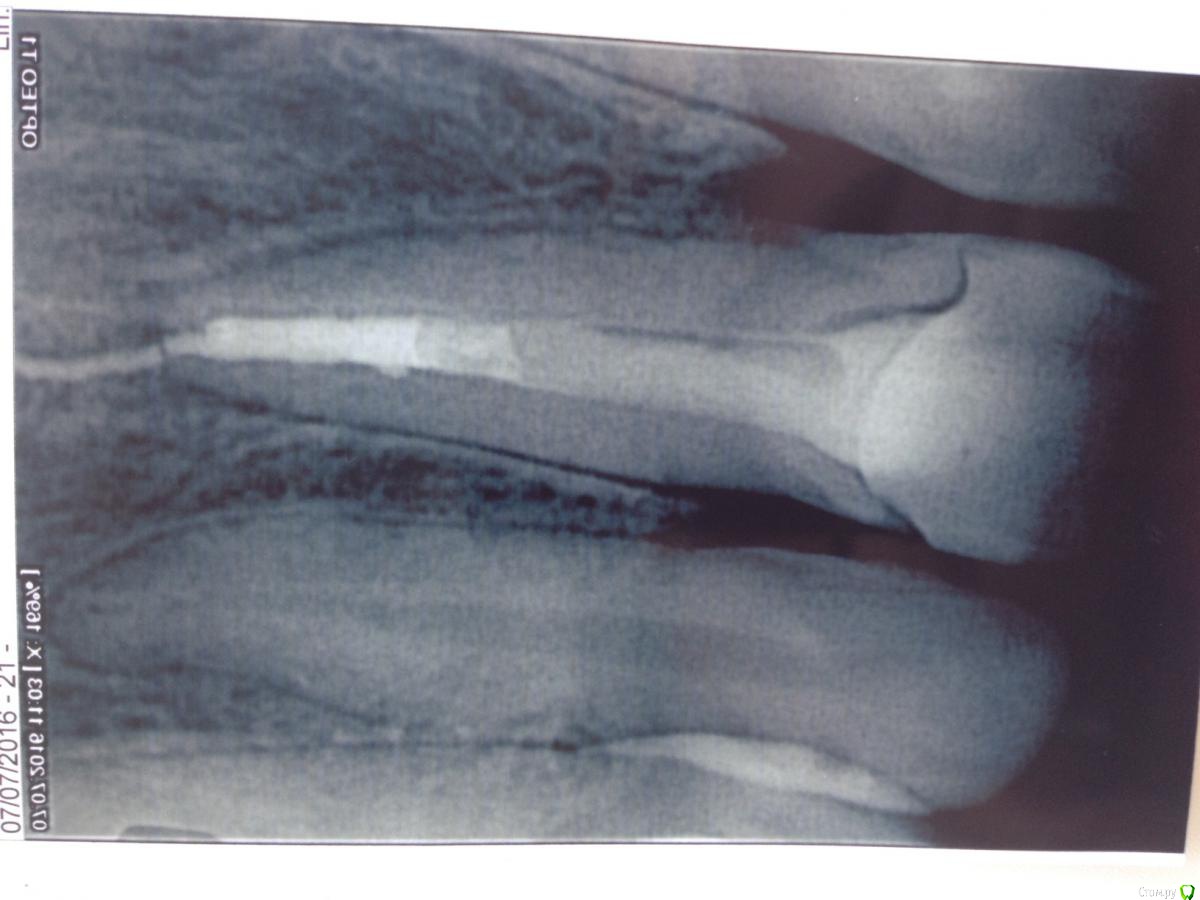

*Katerina* Опубликовано 16 июля, 2016 Поделиться Опубликовано 16 июля, 2016 (изменено) Добрый день, дорогие врачи ) Очень нуждаюсь в вашей профессиональной консультации. Две недели назад был очень сильный удар по передним зубам, в результате которого треснула верхняя единица! Многострадальный зуб был уже депульпирован и установлен штифт, пломба со штифтом целые, треснула передняя стенка зуба (Трещина глубокая, на 3мм ниже уровня десны( внешне зуб выглядит целым). Мне предлагают два варианта: удаление и имплантация или восстановление остатков зуба с вкладкой и коронкой? Снимок выложу Изменено 16 июля, 2016 пользователем *Katerina* Ссылка на комментарий

red_butler Опубликовано 16 июля, 2016 Поделиться Опубликовано 16 июля, 2016 По этому снимку не возможно понять как проходит линия перелома. Нужен очный осмотр. Ссылка на комментарий